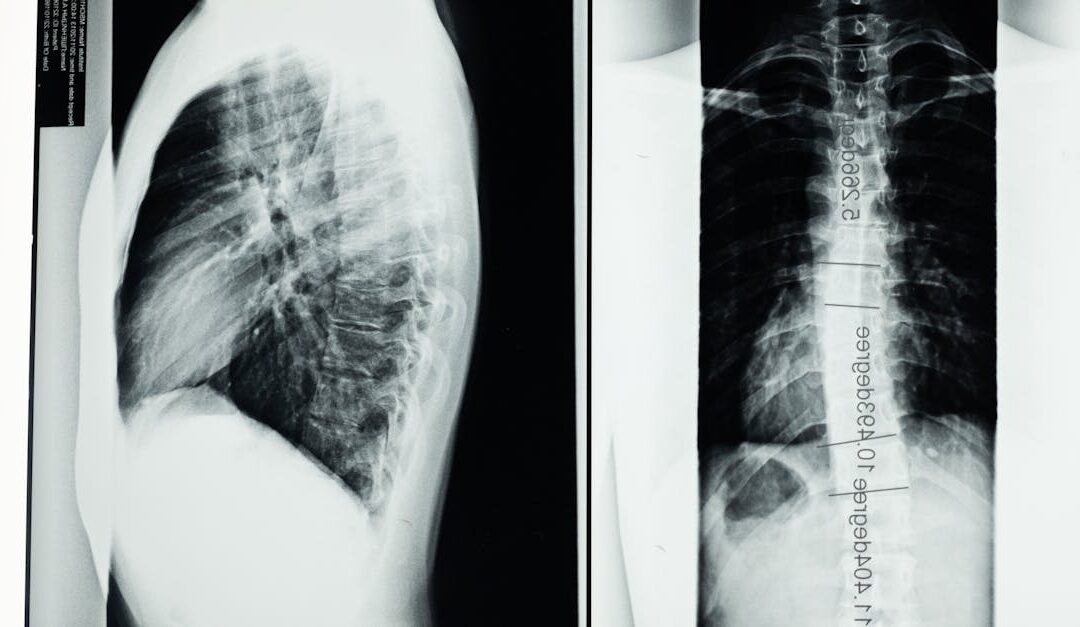

<pBack pain can be a signal that needs careful attention, especially when it comes on suddenly and is localized near the spine. If you live in Clark, NJ or Manhattan, NY, understanding when back pain might indicate a compression fracture helps you decide whether to...